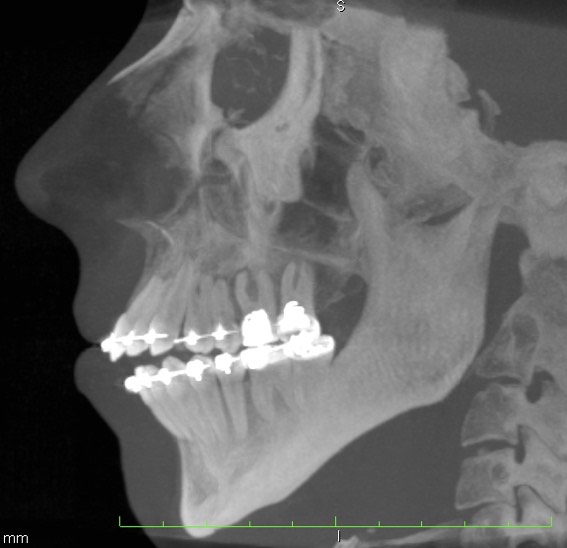

134. Представлена компьютерная томограмма пациента с _____ типом роста лицевого черепа